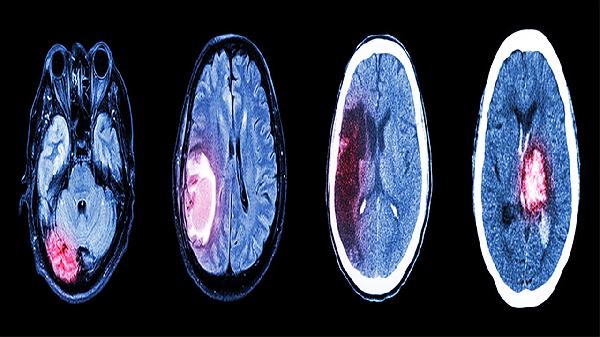

脑蛋白水解物片是从新鲜健康猪大脑组织中提取出的一种活性肽类水解物,本品含有多种氨基酸、卵磷脂、脑磷脂及肽类神经生长因子等。常用于改善失眠、记忆力下降、头痛、头晕及烦躁等症状,可促进脑外伤后遗症,脑血管疾病后遗症,脑炎后遗症,急性脑梗塞和急性脑外伤的康复。